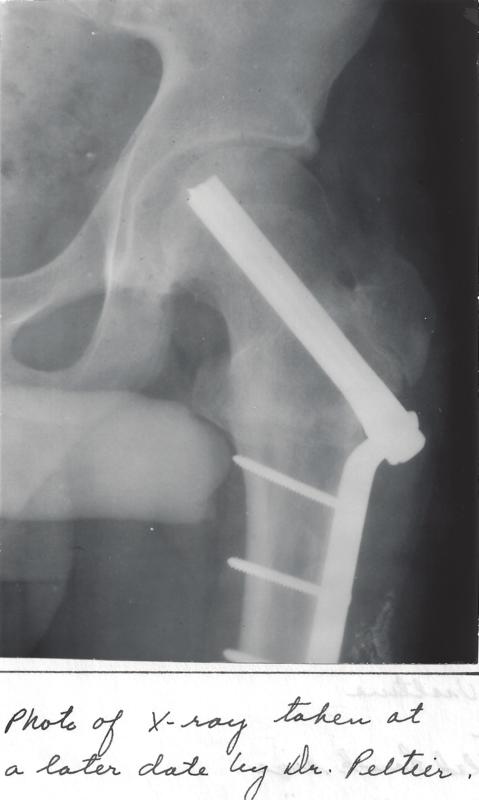

ku-bee:4842-60